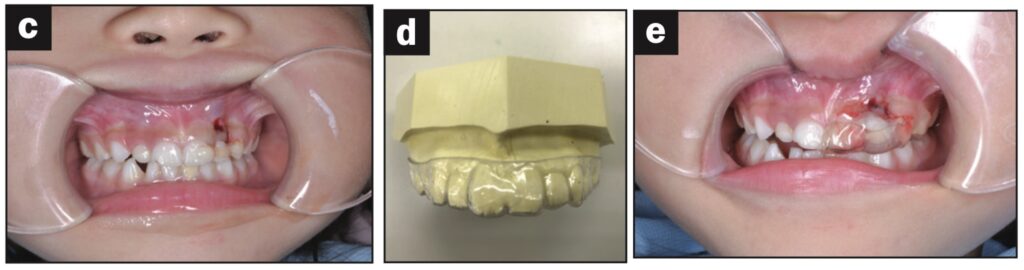

Bệnh nhân nữ 24 tuổi bị ngã khiến răng cửa giữa hàm trên bên trái bị lệch sang một bên. Sáng hôm sau, bệnh nhân đến phòng khám, được cố định bằng composite quang trùng hợp và lấy dấu.

Sáu tiếng sau, bệnh nhân quay lại và nhận hàm duy trì.

Bệnh nhân được hướng dẫn đeo hàm duy trì cả ngày trừ khi đánh răng. Các thử nghiệm độ sống tủy được thực hiện sau 1, 7, 14 và 21 ngày. Kiểm tra độ lung lay răng, gõ, sờ, thử tủy EPT và chụp X quang sau 28 ngày. Răng có độ lung lay +1 theo chiều ngoài trong và không có đáp ứng với thử nghiệm tủy EPT.

Ba tháng sau, răng đã được trám phục hồi và đáp ứng EPT (8/10). Tại thời điểm tái khám sau 4 tháng, răng đáp ứng với EPT (4/10). Sau 5 tháng, ghi nhận có lỗ dò. Răng không đáp ứng với EPT. Tổn thương quanh chóp được nhìn thấy trên X quang.

Răng được chẩn đoán là hoại tử tủy và điều trị tủy được thực hiện trong 2 lần hẹn. Một tháng sau (6 tháng sau khi chấn thương xảy ra), lỗ dò biến mất và chụp X quang cho thấy quá trình lành thương (hình 2).